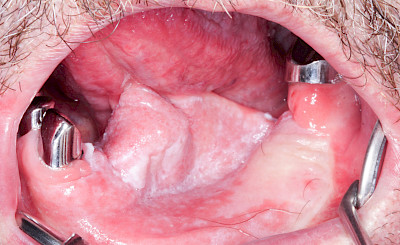

Lichen

Oraler lichen mucosae ist eine chronische, nicht-ansteckende Entzündung der Schleimhaut, wahrscheinlich autoimmun bedingt. Sie kann Wochen bis Jahre bestehen und sich spontan zurückbilden. Es werden zwei Formen unterschieden:

- Retikulär (netzförmig: Lichen planus) mit weißlichen Epithelveränderungen (Wickhamsche Streifen). Entartungsrisiko: 0,4–2,5 %

- Erosiv-atrophisch (ausgewaschen-verkümmert: Lichen erosivus) mit weißlichen, rötlichen, teilweise pseudomembranösen Schleimhauterosionen. Schmerzhaft, leicht blutend, Entartungsrisiko im Vergleich zu Lichen planus deutlich erhöht

Neben einer gesunden Ernährung (Vitamine, Mineralien) sollte vor allem bei der erosiven Form auf scharfe Gewürze, Fruchtsäuren sowie Alkohol oder Tabak verzichtet werden, um die Schleimhaut nicht zusätzlich zu reizen.

Außer der chirurgischen Entfernung (Exzision) oder Laserung kommen im Vorfeld häufig Glukokortikoide (z. B. Cortison) zum Einsatz: Entweder lokal als Salben bzw. Spüllösungen oder intravenös als Cortison-Stoßtherapie.

Orale lichenoide Läsionen (OLL) sind häufig im Nahbereich von Amalgamfüllungen oder von metallischem Zahnersatz zu beobachten. In diesen Fällen sollte ein Zahnarzt hinzugezogen werden, wobei der Austausch der Restauration sehr kritisch abzuwägen ist.